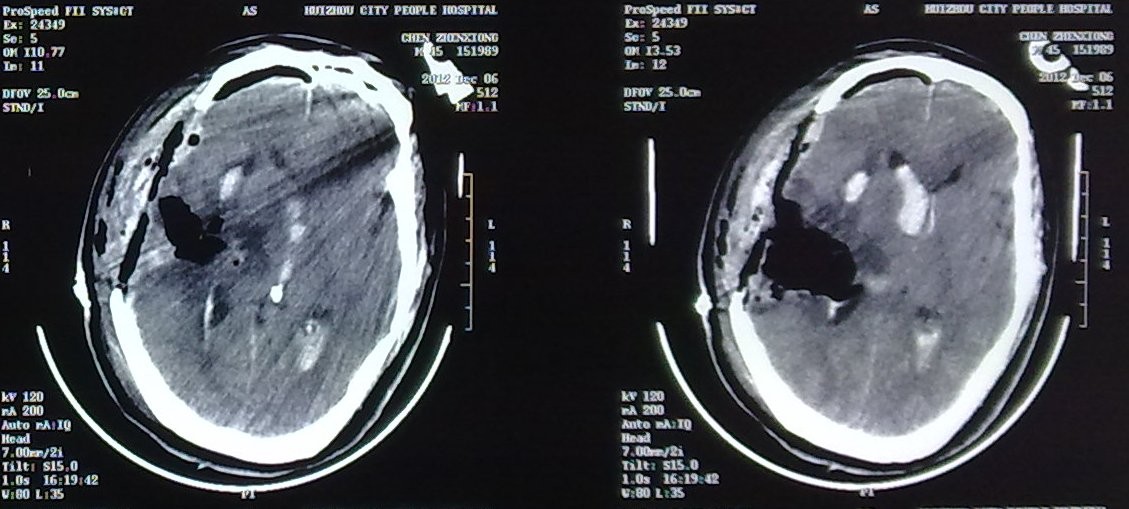

2、显微手术完全清除血肿。

3、显微手术。